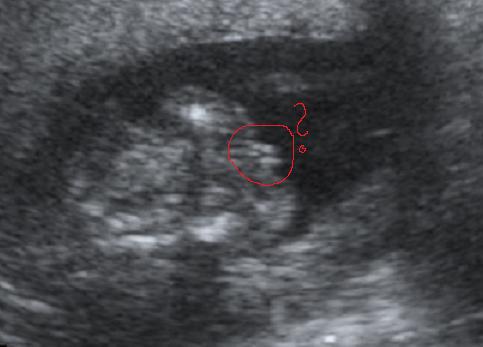

Holnap meg megyek cukorterhelésre, meg vizsgálatra. Gondoljatok rám. Főleg azért, mert tejet kell(ene) inni, de attól undorodom. És nem tudom mi lesz. Most akkor leveszik a vért, vagy van valami alternatív megoldás, nem tudom, pedig kérdezgettem mindenfelé, hogy ilyenkor mi van. Attól félek, hogy kifogok valami bunkó vérvételis csajt/pasit, és majd jól leteremtenek, hogy akkor mit akarok itt, vagy ilyesmi. A cukros lötyit jobban meginnám, mint a tejet. De az itt nincs!